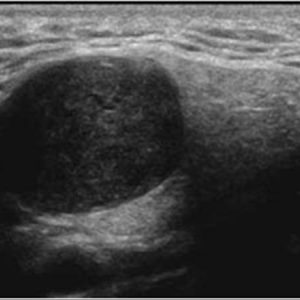

U tuyến nước bọt

Lượt xem: 170» 17-01-2021 -

U tuyến nước bọt

Lượt xem: 174» 17-01-2021 -

U tuyến nước bọt

Lượt xem: 149» 17-01-2021 -

U tuyến nước bọt

Lượt xem: 147» 17-01-2021 -

U tuyến nước bọt

Lượt xem: 146» 17-01-2021 -

U tuyến nước bọt

Lượt xem: 151» 17-01-2021 -

U tuyến nước bọt

Lượt xem: 146» 17-01-2021 -

U tuyến nước bọt

Lượt xem: 136» 17-01-2021 -

U tuyến nước bọt

Lượt xem: 132» 17-01-2021 -

U tuyến nước bọt

Lượt xem: 209» 17-01-2021 -

U tuyến nước bọt

Lượt xem: 150» 17-01-2021 -

U tuyến nước bọt

Lượt xem: 185» 17-01-2021 -

U tuyến nước bọt

Lượt xem: 151» 17-01-2021 -

U tuyến nước bọt

Lượt xem: 212» 17-01-2021 -